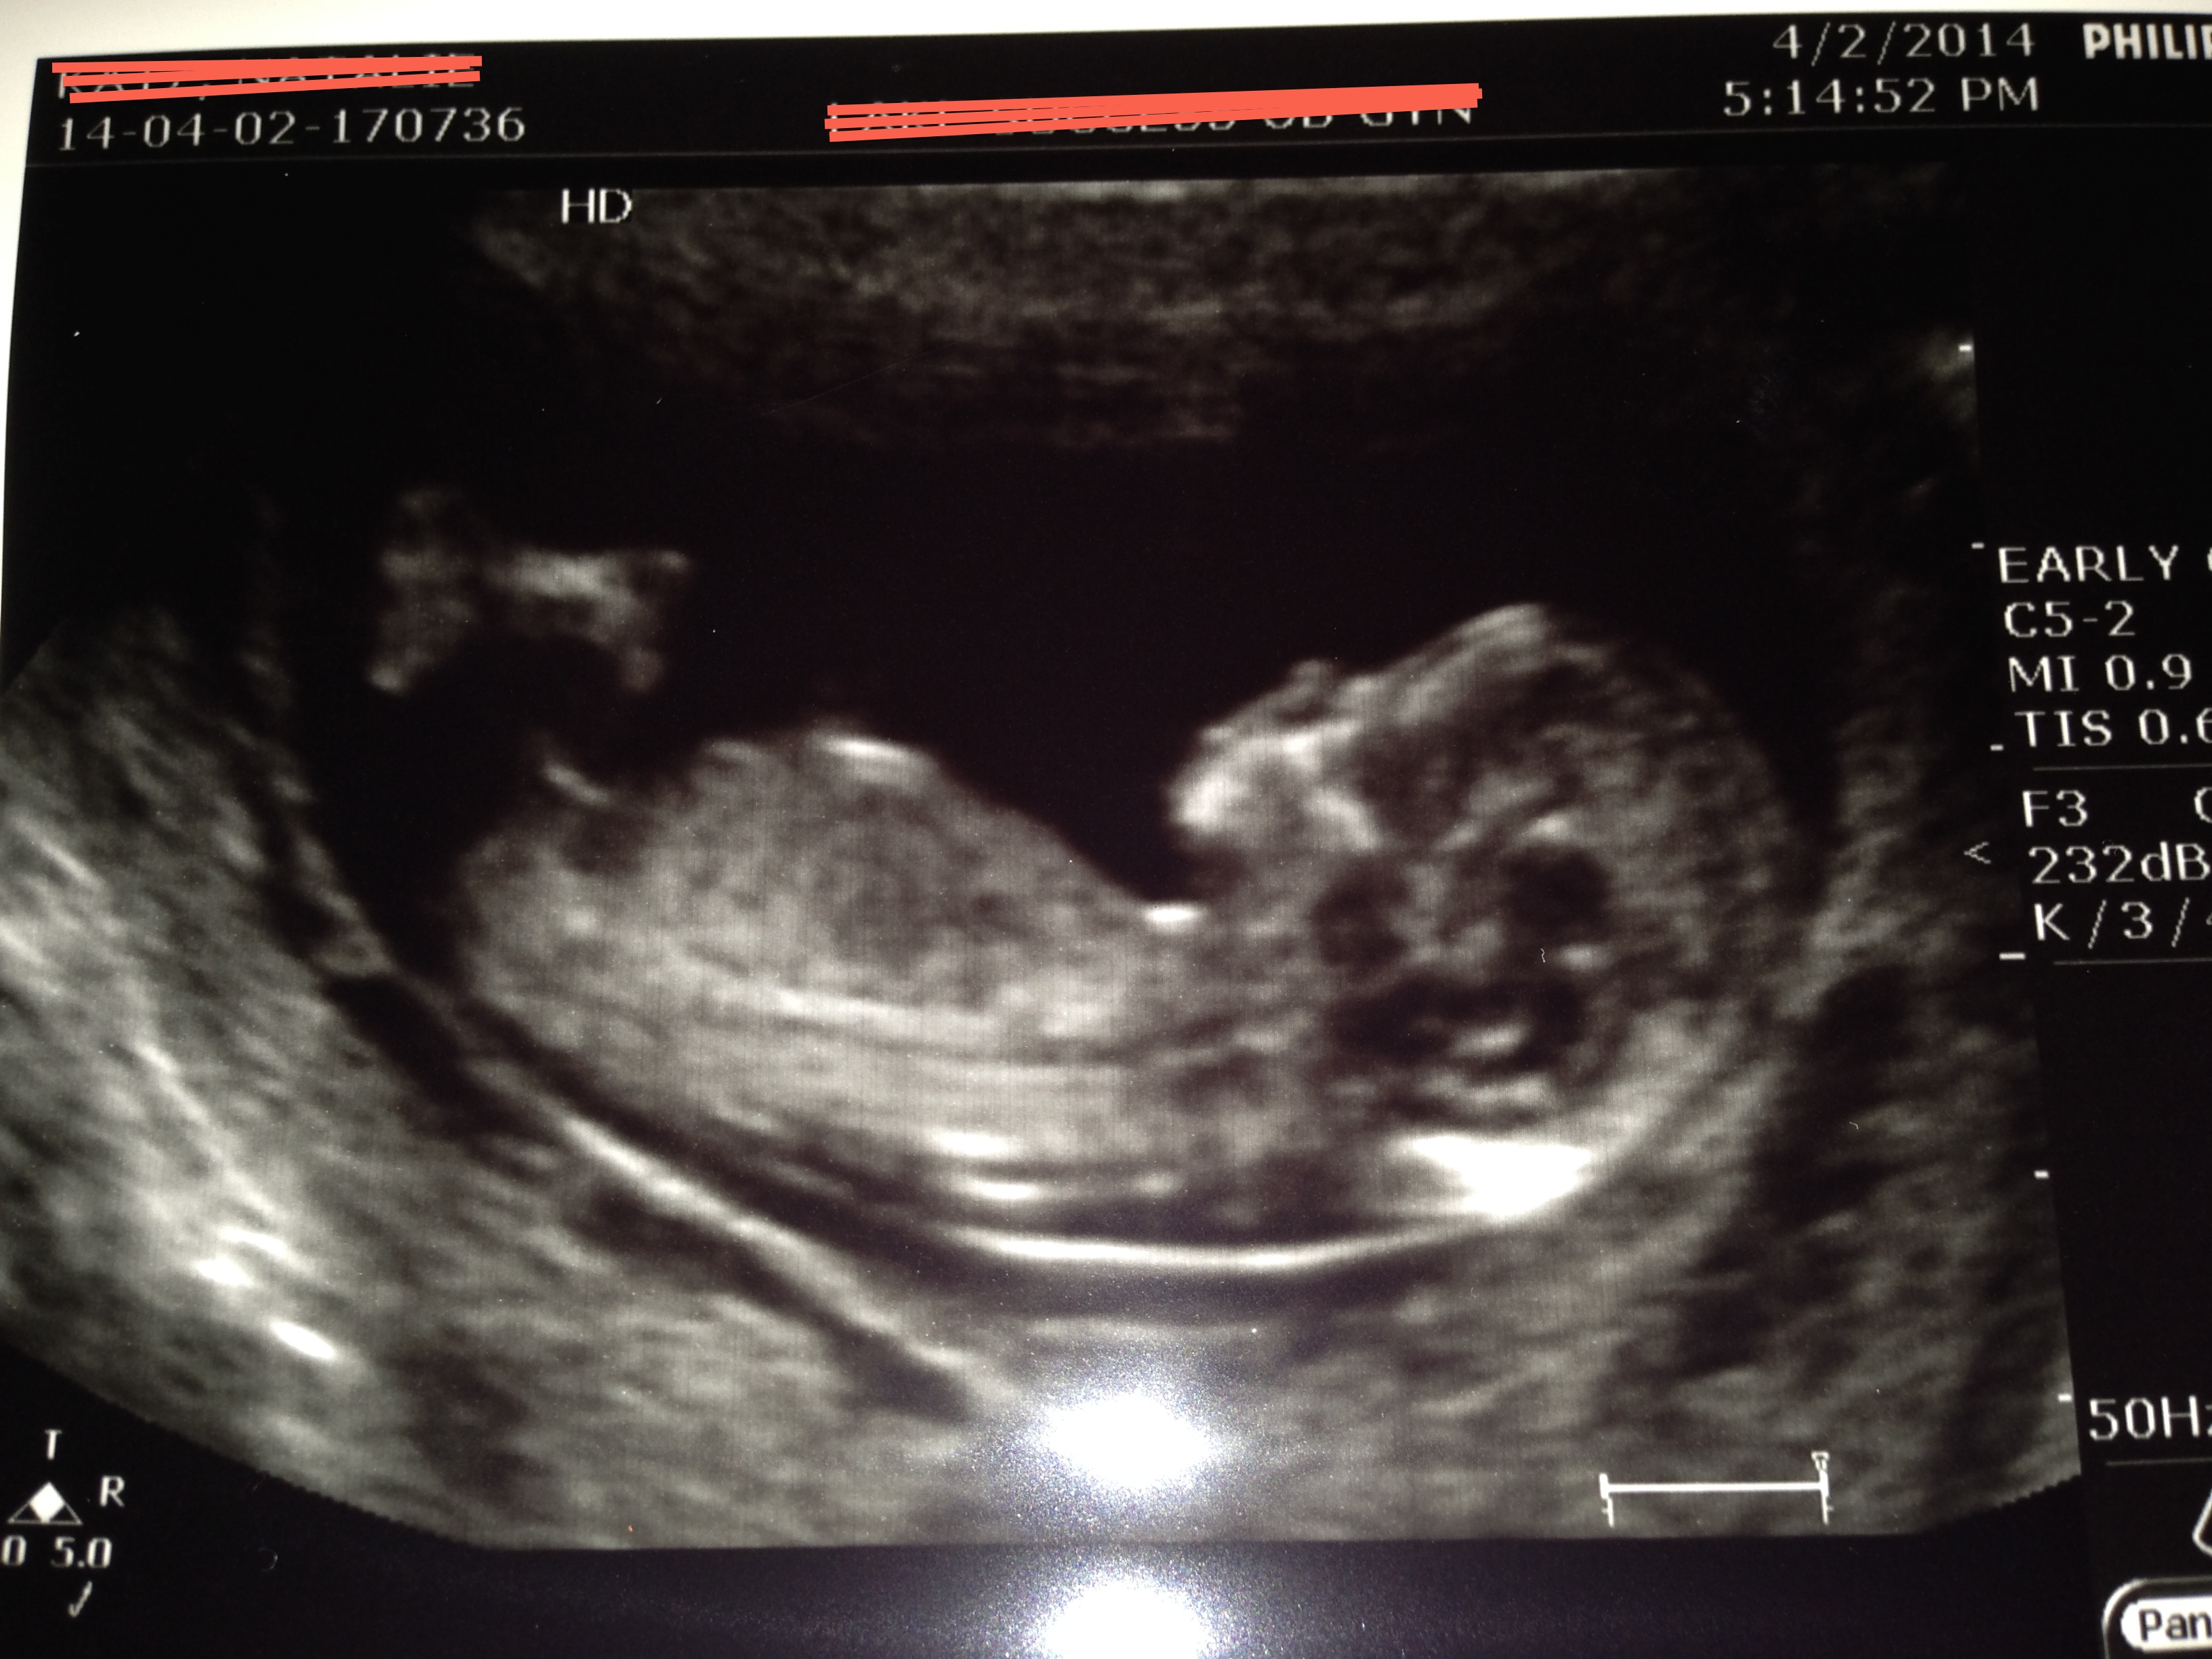

This is for a friend. At first I thought girl, but then I thought I saw stacking. What do you think? She is 12 weeks exactly.

The new pic appears to have a very boy nub if that in fact is the nub:)

Very boy

The new pics look boyish to me, but what I see might be part of a leg or cord, so just a tentative guess xx

Boy!

I think boy, too.